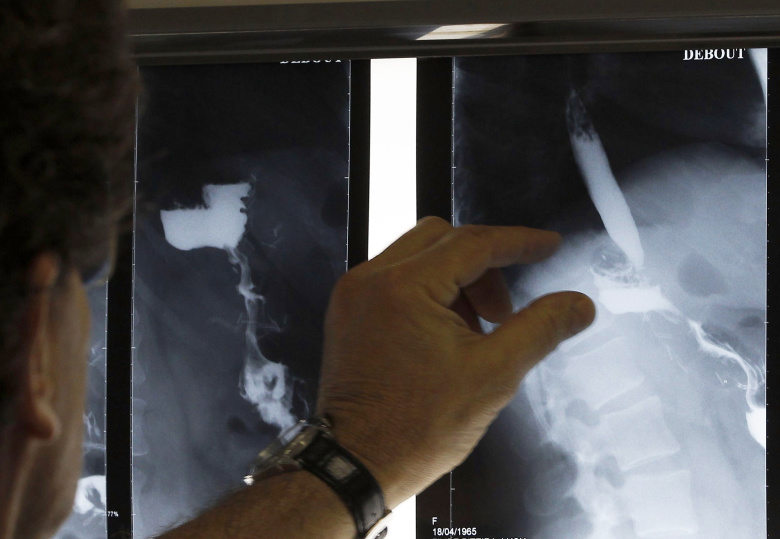

Ожирение – проблема, которая беспокоит врачей по всему миру. Россия не отстает от развитых стран, и сегодня в нашей стране каждый четвертый имеет лишний вес, а 30% страдают собственно ожирением. Слишком большой избыточный вес приводит к различным хроническим заболеваниям – сахарному диабету, сонному апноэ, болезням позвоночника и суставов, нарушению половой функции и даже психологическим расстройствам. Когда ожирение становится болезненным (морбидным), врачи предлагают сделать операцию по уменьшению объема желудка, которая действительно помогает не только снизить вес, но и позволяет не набрать его вновь. Большинство считает, что такие операции просто уменьшают размер желудка, что не позволяет человеку много есть, но ученые обнаружили и множество других важных последствий для организма. Корреспондент New York Times Джина Колата год наблюдала за двумя американцами, решившимися на операцию, чтобы похудеть. В своей статье она рассказывает, что с ними произошло за это время и как изменилась их жизнь.